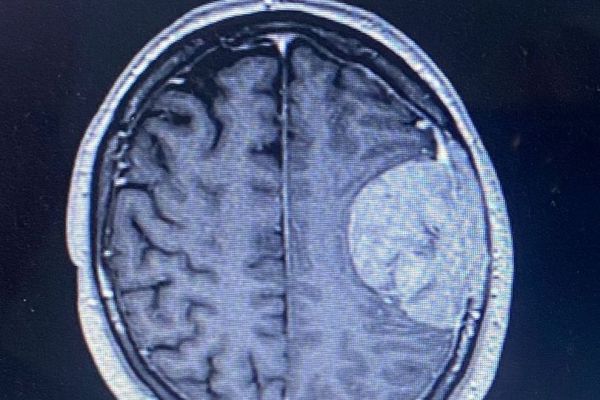

But it was actually a brain tumour that was attached to his membrane and skull.

As the highways inspector’s speech fluctuated, he was prescribed steroids. And surgeons advised that because there was no evidence of cancer elsewhere, it was likely to be a slow-growing tumour that could’ve been there silently for years.

With little-to-no other options, Bev agreed for her husband to go through with the procedure. After three weeks, on 9 May, the tumour was successfully removed. Sadly, though, it hadn’t grown into his brain and was instead attached to his membrane, as well as his skull.

He had to have the part affected removed and reconstructed using bone cement. I t was then found that he had suffered a stroke in the area responsible for speech and language. Now, 10 months on, it’s still a daily battle to speak.